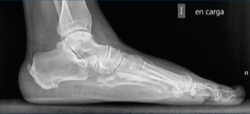

Figura 4. Imagen fluoroscópica de la fresa suelta introducida y su correspondencia en cirugía.

Ayudándose del mosquito para separar las partes blandas, se introduce una fresa Shannon 2 o 3 × 20 mm (FH Orthopedics, Mulhouse, Francia) en el vértice de la V. Comprobada la correcta posición de la fresa en la fluoroscopia (desconectando el motor de la fresa) (Figura 4), esta se avanza perpendicularmente al eje del calcáneo hasta atravesar la segunda cortical. Inclinando la fresa se pueden obtener diferentes desplazamientos, si bien, para conseguir un mayor desplazamiento, se recomienda avanzar perpendicularmente al eje. Si se quiere conseguir cierto efecto de descenso además de medialización de la tuberosidad se dirigiría la fresa en dirección de dorsolateral a plantomedial unos 15-30° respecto a la perpendicular del eje del calcáneo. Si lo que se quiere es obtener un efecto de elevación (beneficioso en el cavo posterior), la dirección sería la contraria, es decir, de lateroplantar a dorsomedial. Se podría obtener también acortamiento del calcáneo si la fresa se dirige de lateral distal a medial proximal, e incluso un alargamiento (de lateral proximal a medial distal), aunque esto último dificultaría el desplazamiento por la tensión de los tejidos(13).

Figura 5. Imagen fluoroscópica del trazo dorsal de la osteotomía y su correspondencia en cirugía.

La fresa se coloca en línea con el trazo de osteotomía dibujado en la piel, primero el dorsal y después el plantar (Figuras 5 y 6), y va cortando la pared lateral y el hueso esponjoso del calcáneo y progresando paulatinamente hasta alcanzar la segunda cortical y cortarla cuidadosamente. Se recomienda no superar en 6.000 rpm la velocidad de la fresa para evitar la osteonecrosis térmica. A pesar de que el procedimiento se realiza sin isquemia para que la sangre refrigere el calor de la fresa, se recomienda que el ayudante aporte suero salino para contribuir a tal efecto.

Figura 6. Imagen fluoroscópica del trazo plantar de la osteotomía y su correspondencia en cirugía.

Se comprueba si la osteotomía es completa; si es así, la tuberosidad del calcáneo podrá manipularse hacia lateral y medial. Si no se consigue mover, será necesario repasar la osteotomía con la fresa palpando y fresando las posibles zonas no osteotomizadas que queden.